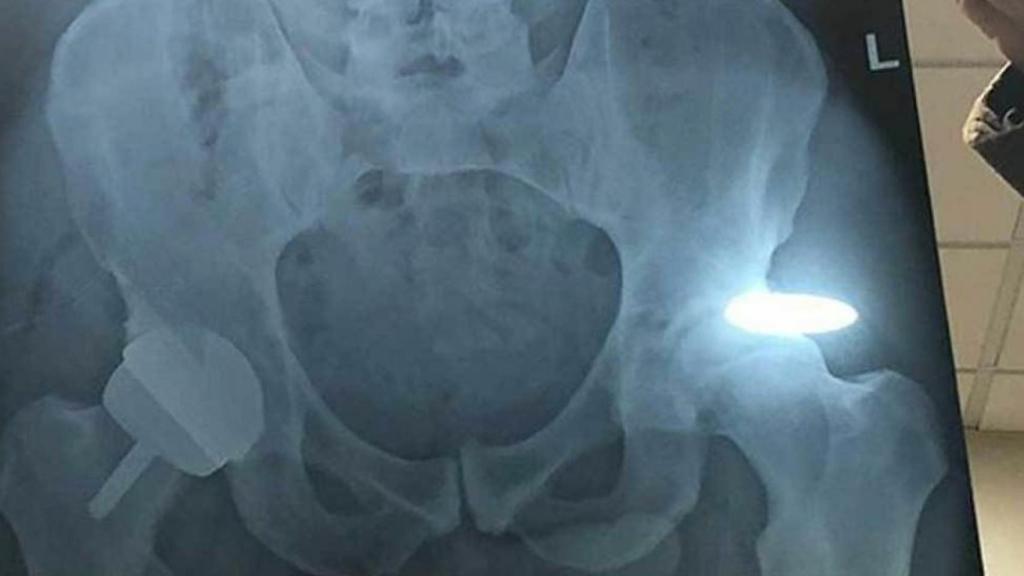

La radiografía de la cadera de Andy Murray

El tenista escocés publicó una fotografía tras su operación y adjuntó el negativo de la cadena, que tuvo mucha repercusión en las redes sociales.

El tenista Andy Murray se sometió a una operación de cadera el pasado martes tras anunciar su decisión de retirarse este año en la previa del Abierto de Australia debido a sus dolores y lesiones que lleva arrastrando durante más de 18 meses y que no le han permitido dar su máximo nivel en las competiciones.

El escocés público una fotografía en su cuenta de Instagram explicando que "con suerte, este será el final de mi dolor en la cadera" y que ahora tiene "una cadera de metal". Junto a la imagen en el hospital tras la operación, adjuntó la radiografía de su cadera, que se ha vuelto viral en Inglaterra. Varios aficionados se han dado cuenta que en ella aparece el pene de Andy Murray.

"Andy Murray accidentalmente colocando su pene (en una foto de rayos X) en Instagram es un accidente hilarante o su malvado sentido del humor", es alguno de los comentarios que han escrito los aficionados a través de Twitter. "¿Soy el único que encuentra el 'tesoro nacional' del vago de Andy Murray, pequeño pene desconcertante?", señaló otro seguidor del tenista.